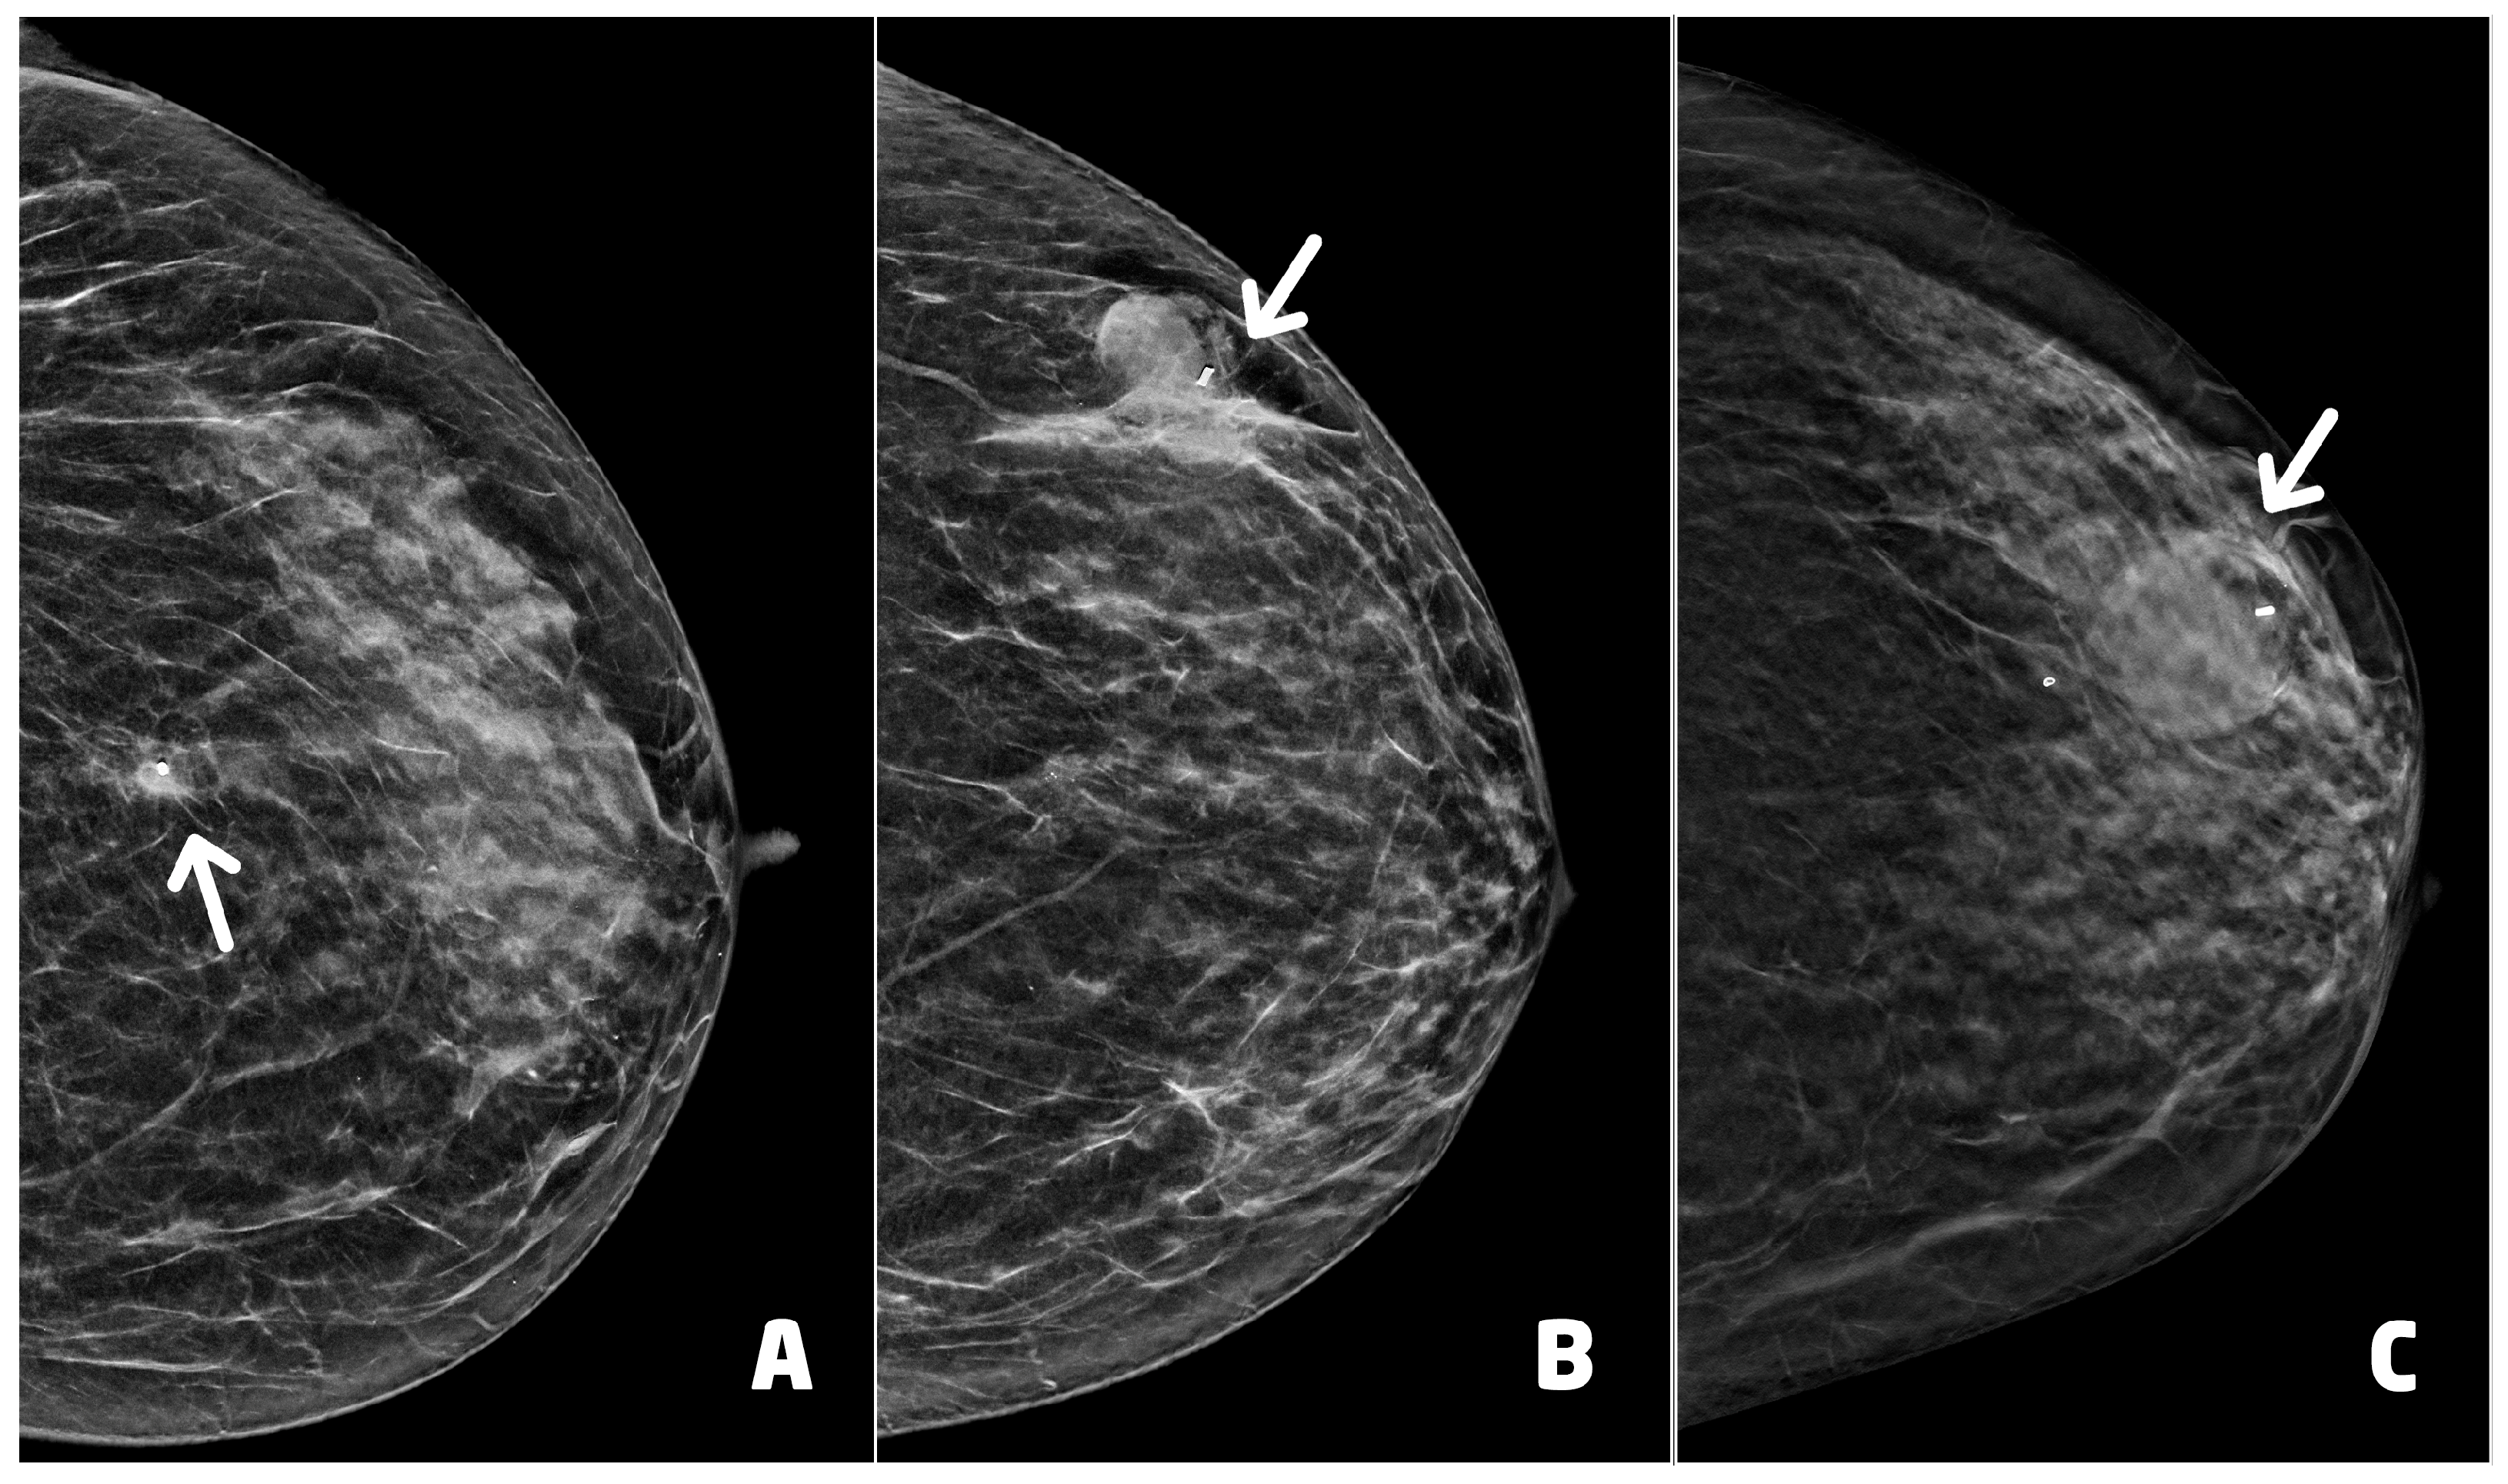

Post-procedural hematoma was found in 12 cases (14.1%) (Figure 5). According to the classification proposed by Schaefer et al. [24], two hematomas were classified as moderate while 10 as mild. Nine hematomas were found in women who underwent VABB with a 9 G needle, while the remaining three underwent VABB with a 12 G needle.

The post-procedural clip was correctly positioned in 75 of 85 procedures (88.2%). The clip was migrated cranially in four cases, caudally in four cases and externally to lesion in the remaining two cases. One woman showed both hematoma and migration of the clip after a procedure performed with a 9 G needle.

Figure 5. Post-procedural hematomas and clip placement (white arrows): (A) 55 year-old woman (see Figure 4C), clip in correct position with mild hematoma, two days after the procedure; (B) 62 year-old woman with lobular carcinoma in situ of the left breast, clip in correct position with moderate hematoma, two days after the procedure; (C) 66 year-old woman (see Figure 4A), clip in correct position with moderate hematoma.